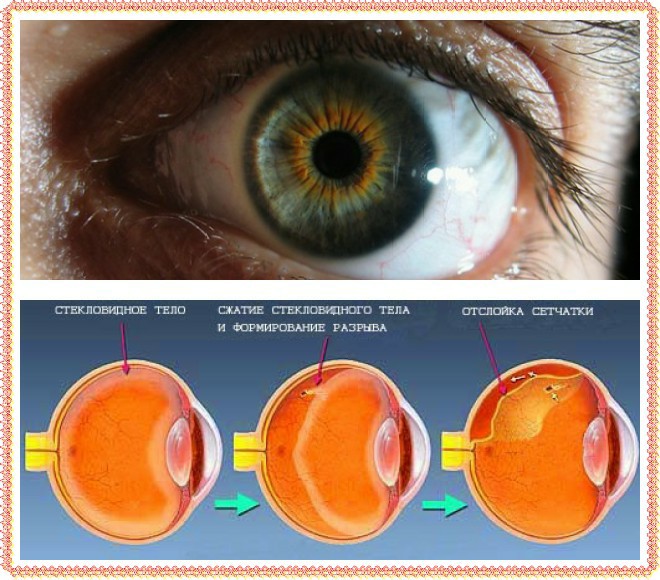

Изображения и анатомия сетчатки глаза